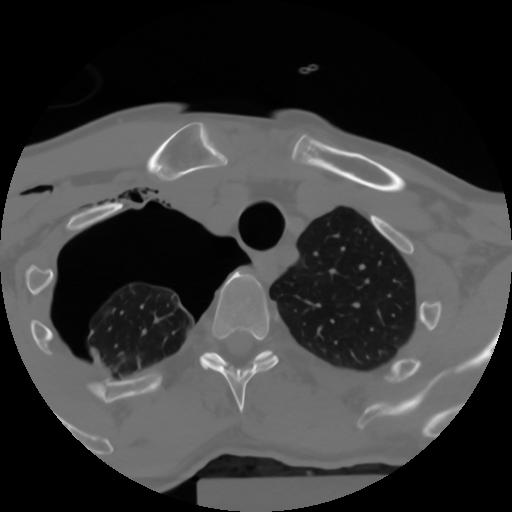

10 P.BLANDAS,,Axial,2.0,P.BLANDAS,,